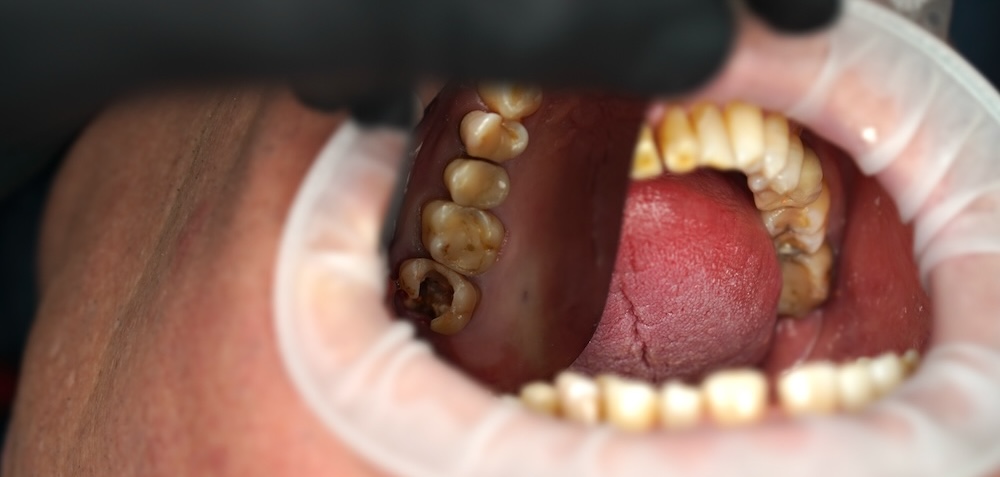

Комп’ютерна томографія та огляд показали, що зуби розташовані неправильно, прикус порушений, а навантаження розподіляється нерівномірно. Саме через це передні зуби поступово перевантажувались і почали сколюватись. Додатково виявили карієс, запалення в раніше пролікованих зубах (періодонтит — це коли інфекція виходить за межі кореня зуба і підтримує хронічне запалення в кістці), а також відсутність 36 зуба, що ще більше порушувало баланс при жуванні.

Окремою проблемою був 12 зуб із металокерамічною коронкою. Ззовні він виглядав більш-менш стабільно, але під коронкою зуб був значно зруйнований.